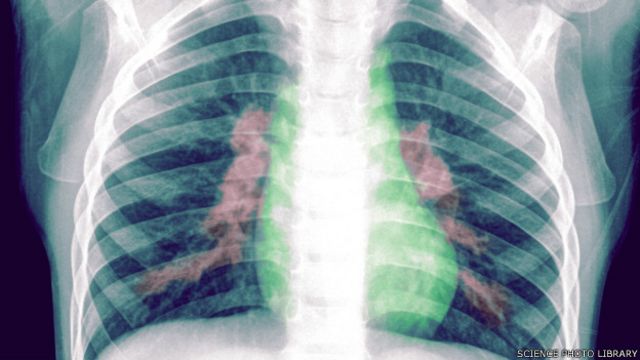

سکاروی د سږو او تنفسي غړو التهابي ناروغي ده چې ډېری وخت انتاني لاملونه لري

سکاروی د سږو او تنفسي غړو التهابي ناروغي ده چې ډېری وخت انتاني لاملونه لري.

په سکاروي اخته ناروغان، ټوخی، تبه، او سالنډی لري، په عمومي توګه ناسازه وی، او که پر وخت ونه درملل شي وژونکې خړپړتیاوې ورسره ملګرې وي.